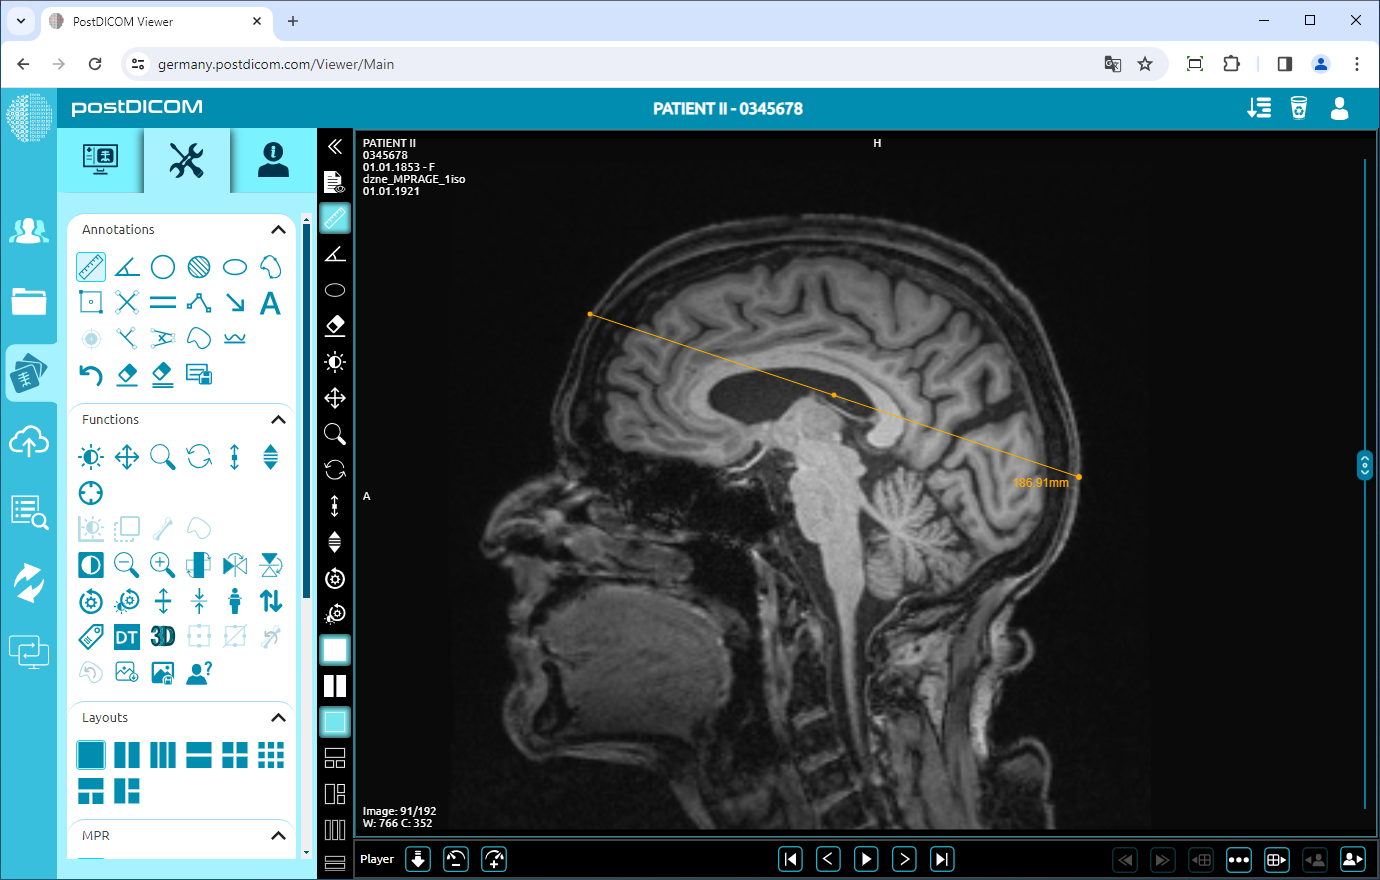

When you click on the icon, it will turn into blue color and a ruler sign will be shown at the bottom of your mouse pointer. Click on the starting point of the distance you want to measure and move your mouse to the endpoint. Until you click, the distance will appear in blue. Click on the endpoint of the distance and then it will turn into yellow. You will see the distance value next to the end point which is the actual value of the measured distance.

If you need to measure another distance, click on the start and end points of the new measurement. Right-click to exit from the measurement tool. The mouse pointer will return to the default function.

In this way, you can measure any distance on the view with its actual value.